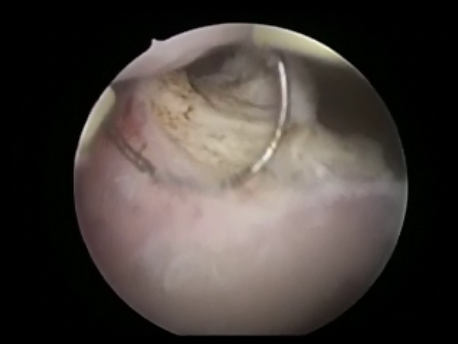

- Intrauterine foreign bodies: Missing copper T embedded in the uterine wall or retained fetal bones or pregnancy following a miscarriage can contribute to irregular bleeding, infection or subfertility.